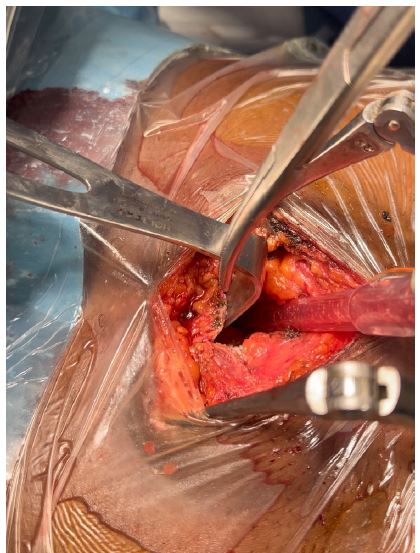

Figure 3: Showing surgical site with pericardiotomy.

Figure 4: Showing surgical site with curved clamp showing amputated xiphoid process

Patient was placed under general anesthesia, intubated and placed in the supine position on the surgical bed. Routing disinfection and surgical prepping was done. A subxiphoid median incision starting from xiphoid process to about 7 cm inferiorly was made. Subcutaneous and muscle fascia dissected and the xiphoid process amputated for better exposure of the pericardium. The bulging pericardium seen with a pericardiotomy made gently on the pericardium. Approximately 2 Liters of serohematic pericardial fluid was drained and a pericardial drain was placed in the pericardial space and connected to a self-expanding vacuum drain which was intended to drain the rest of the pericardial fluid. A biopsy of the pericardium was collected alongside 10cc of pericardial fluid and send for histo-cytology studies to determine the etiology of the effusion. Two thoracic drains were also placed and suture wounds closed up according to standard fashion and patient was taken to the surgical ward afterwards. Post operatively, cardiologist and infectious disease consults were requested for the patient. Post operative follow up was done. Histo-cytology results confirming TB as the etiology of the effusion. Patient was placed on anti TB medimedications by the infectious disease doctor and patient improved clinically and symptomatically with drained not producing anymore. Patient was later discharged 10 days post operatively and reviewed 2 weeks after with follow up cardiac echo and chest Xray not showing any pericardial effusion and pleural effusion respectively.